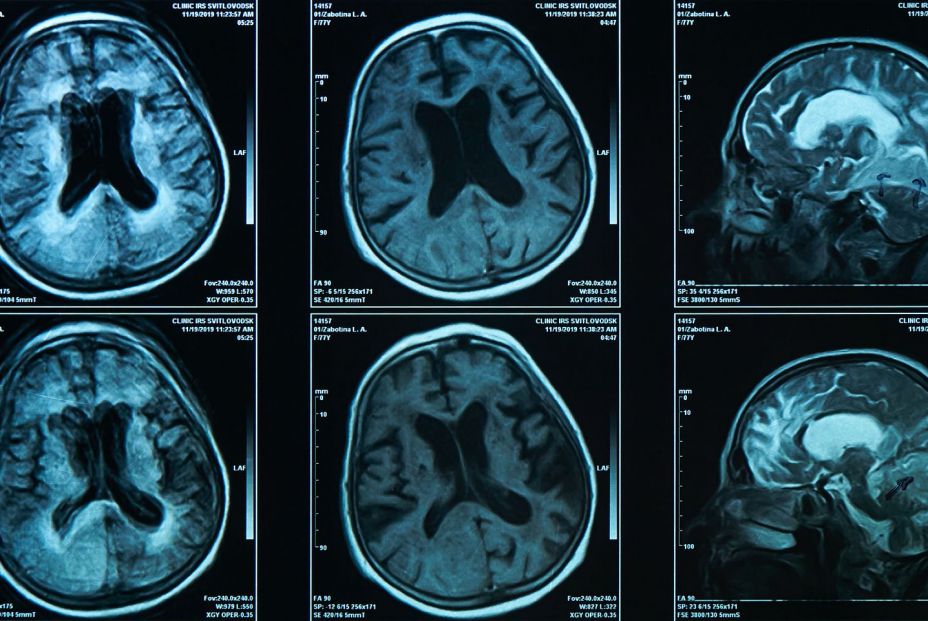

La terapia con células madre podría proteger contra la pérdida de memoria del alzhéimer

Un estudio de la Universidad de California en San Diego (Estados Unidos) ha demostrado que los trasplantes de células madre hematopoyéticas pueden proteger contra la pérdida de memoria, la neuroinflamación y la acumulación de B-amiloide en ratones con alzhéimer.